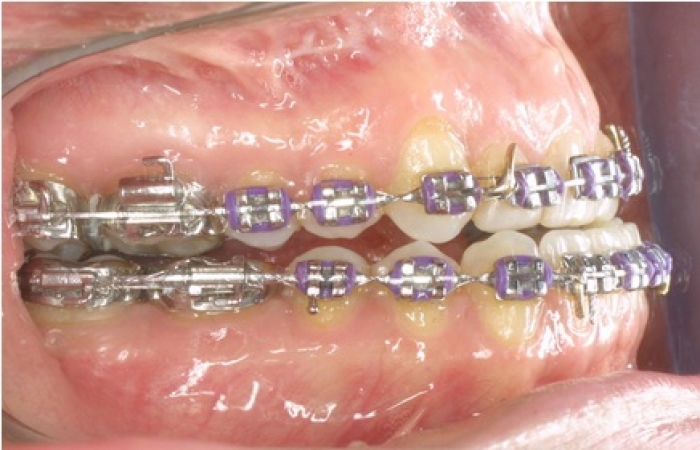

Imagem inicial - Clínica Cliniface

Imagem inicial

Imagem após cirurgia ortognática - Clínica Cliniface

Imagem após cirurgia ortognática